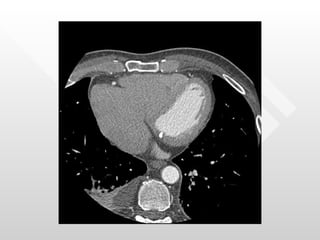

Normal pericardial thickness Multiple adhesions between the pericardium and the heart RV directly below the sternum

Normal pericardial thicknessMultiple adhesions between the pericardium and the heart RV directly below the sternum